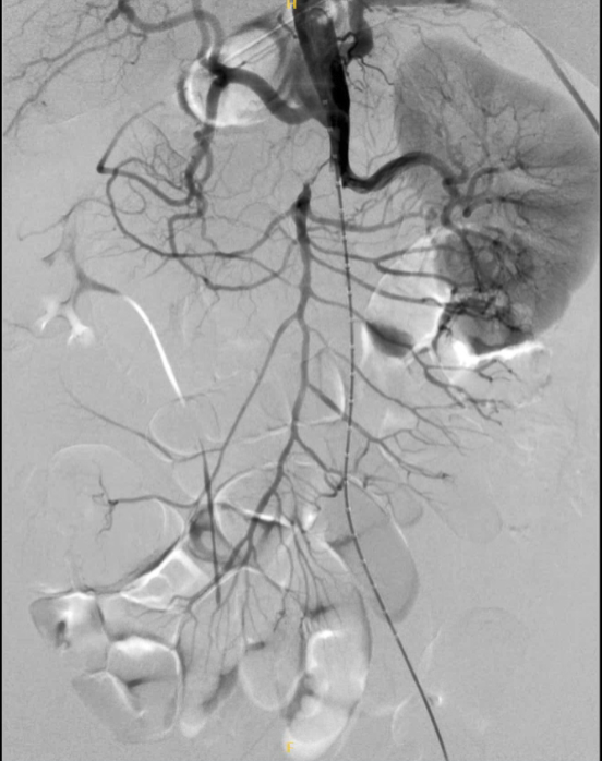

通过下面4个具体病例进一步说明TEVAR在治疗复杂型B型主动脉夹层中的治疗原则、注意事项及应用。

34岁男性,SMI灌注不良,TEVAR后SMA重建

48岁男性,胸腹痛20小时,右下肢一过性麻木,TEVAR治疗